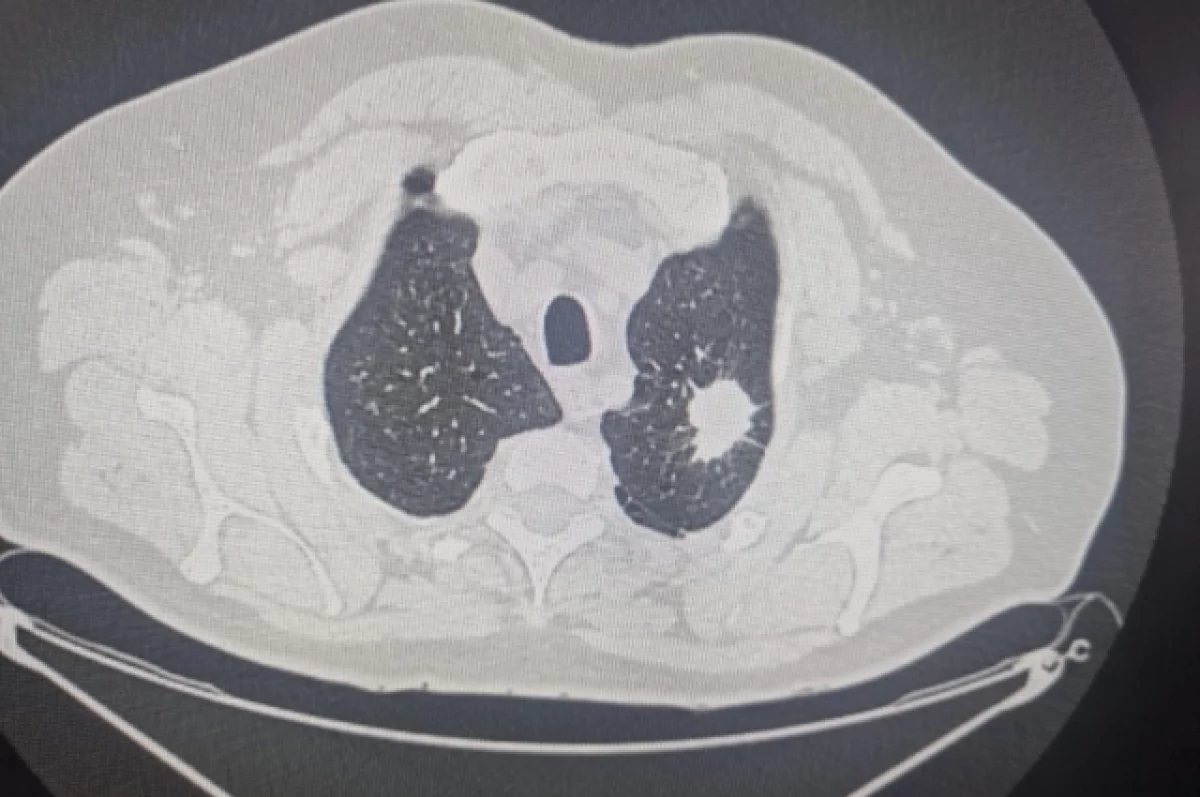

В 2025 году во время диспансеризации в Новосибирской области медики заподозрили онкологические заболевания у 6466 человек. После дополнительных обследований диагноз злокачественной опухоли подтвердился у 1352 пациентов.

Врачи отмечают, в 72% случаев болезнь выявили на первой или второй стадии. Это даёт хорошие шансы на успешное лечение.

Сейчас на учёте у онкологов региона — свыше 96 тысяч человек. Каждый год фиксируется примерно 12 тысяч новых случаев заболевания. Чаще всего врачи диагностируют доброкачественные новообразования кожи, рак молочной железы, предстательной железы и органов дыхания. Большинство заболевших — люди старше 60 лет.